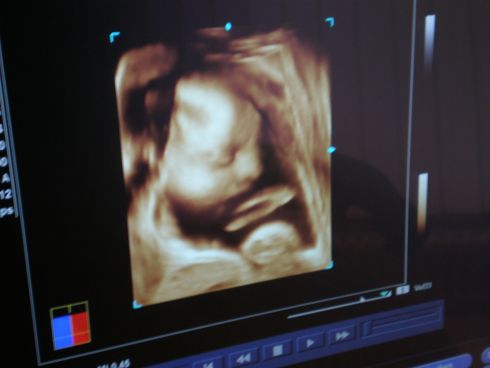

3D / 4D Ultraschall